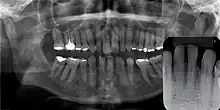

Panoramal radiograph of GCA. Inset: no evidence of bone involvement.

Gingival cyst of adult is a rare condition. The incidence is less than 0.5%. It is formed from the rests of dental lamina.[11] It is found in the soft tissues on the buccal and labial portions of the jaw. It usually occurs on the facial gingiva as a single small flesh colored swelling, sometimes with a bluish hue due to the cystic fluid. Sometimes, it may occur in cluster, either unilaterally or bilaterally or on the lingual surface of the alveolar process. It is most commonly seen in the canine and premolar regions of the mandible, and are sometimes confused with lateral periodontal cysts.[12] It is not normally problematic, but when it grows larger, it can cause some discomfort. It can be removed by simple surgical excision. They are developed late in life, generally up to the sixth decade of age.[1]